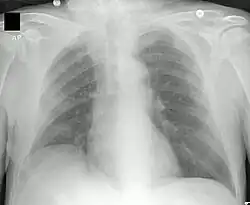

Neumonía apical derecha: en la FQ, la infección crónica da lugar a la destrucción del parénquima pulmonar, ocasionando por último la muerte por insuficiencia respiratoria. | ||

La FQ afecta a múltiples órganos y sistemas, originando secreciones anómalas y espesas de las glándulas exocrinas. La principal causa de morbilidad y mortalidad es la afectación pulmonar, causante del 95 % de los fallecimientos, sobre todo por infecciones repetidas originadas por obstrucción bronquial debida a la secreción de mucosidad muy espesa. Otros órganos afectados son el páncreas y en ocasiones el testículo.[2][3] [4]

Enfermedad pulmonar y sinusal

La enfermedad pulmonar resulta del bloqueo de las vías aéreas más pequeñas con el moco espeso característico de la fibrosis quística. La inflamación y la infección producen daño a los pulmones y cambios estructurales que conducen a una variedad de síntomas. En las etapas iniciales, comúnmente se presentan tos incesante, producción copiosa de flema, y una disminución en la capacidad aeróbica. Muchos de estos síntomas ocurren cuando ciertas bacterias (fundamentalmente, Pseudomonas aeruginosa) que normalmente viven en el moco espeso, crecen en forma descontrolada y causan neumonía. En estados avanzados de la FQ, los cambios en la arquitectura del pulmón producen dificultades respiratorias crónicas.

Otros síntomas incluyen expectoración de sangre o esputo sanguinolento, dilatación crónica de los bronquios o bronquiolos (bronquiectasia), elevación de la presión sanguínea en el pulmón, insuficiencia cardíaca, sensación de no estar recibiendo suficiente oxígeno o disnea, insuficiencia respiratoria y atelectasia; podría requerirse soporte ventilatorio.[8] Además de las infecciones bacterianas más comunes, las personas con FQ desarrollan con mayor facilidad otros tipos de enfermedades respiratorias. Entre estas se encuentra la aspergilosis broncopulmonar alérgica, caracterizada por una respuesta de hipersensibilidad ante un hongo (moho) ordinario del género Aspergillus (Aspergillus fumigatus), que agudiza los problemas respiratorios. Otro ejemplo es la infección con el complejo Mycobacterium avium (MAC), grupo de actinobacterias emparentadas con Mycobacterium tuberculosis, que puede ocasionar daños mayores al pulmón, y que no responde a la terapéutica con antibióticos convencionales.

Existen diversas pruebas para identificar eventuales complicaciones y controlar la evolución de la enfermedad. Las imágenes obtenidas por rayos X y TAC facilitan la detección de signos de lesión o infección en los pulmones. El cultivo de esputo, examinado por microscopio, provee información respecto de cuáles son las bacterias responsables, y permite escoger los antibióticos más efectivos. Las pruebas de función pulmonar miden las capacidades pulmonares, los volúmenes pulmonares y la rapidez con que estos pueden ser movilizados (flujos aéreos). Por medio de tales exámenes, es posible determinar si es procedente un tratamiento con antibióticos o bien evaluar la respuesta al mismo. Los análisis de sangre pueden identificar problemas hepáticos, deficiencias vitamínicas, y revelar la irrupción de la diabetes. Los dispositivos DEXA o DXA (del inglés para ‘absorciometría de rayos X de energía dual’), se utilizan como prueba para determinar la presencia de osteoporosis. Por último, la cuantificación de elastasa fecal, facilita la detección de insuficiencia de enzimas digestivas.